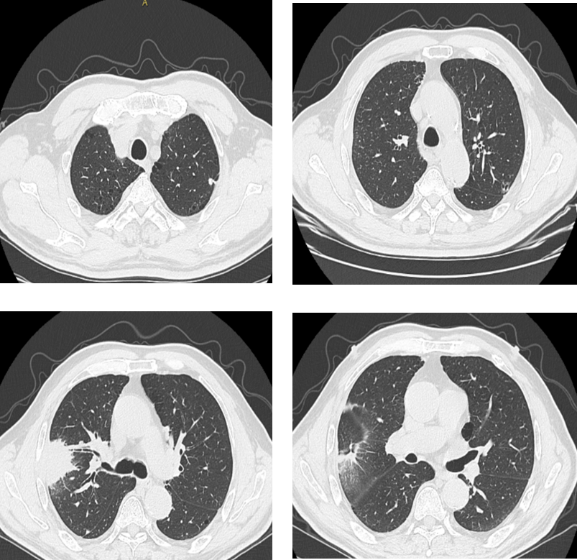

胸部CT:右肺上叶肿块,考虑占位;左肺上叶尖后段厚壁小空洞;两肺上叶肺气肿。

PET-CT:右肺上叶肿块,累及胸膜、胸壁及第4-5前肋,代谢增高;双肺门及纵隔淋巴结代谢增高;左肺上叶尖段空洞代谢增高,不除外转移。

疗效评估:3周期治疗后复查CT,右肺病灶明显缩小,评估为部分缓解(PR),为手术创造了条件。